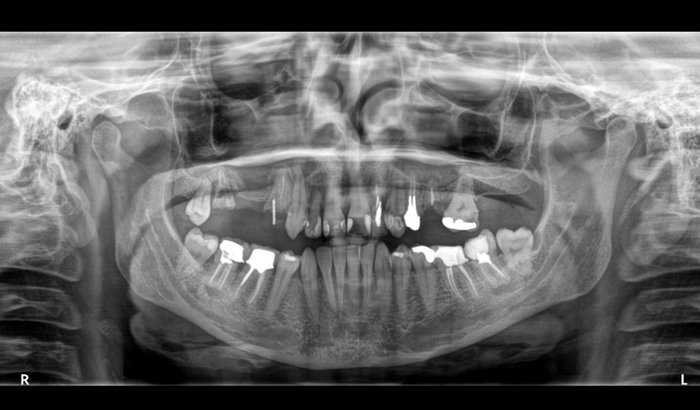

Postei a tomografia e a radiografia panorâmica. Sei que a maioria não vai entender.

Nas fotos é possível perceber que não tenho mtos dentes mais na parte superior. Onde há falhas são raízes expostas e que precisam ser extraídas urgentemente.

A fratura óssea atingiu somente a parte superior, graças à Deus.

Na parte inferior precisa-se fazer pequenos reparos em pequenas fraturas.

A Stiff Person Syndrome (Síndrome da Pessoa Rígida) tem como sintomas em casos raros as fraturas ósseas. Infelizmente, no meu caso, desenvolveu essa questão da fratura óssea na boca.

Já são várias as fraturas! Já tive fraturas em diversas raízes e os poucos dentes que ainda estão intactos já estão com a mobilidade comprometida.